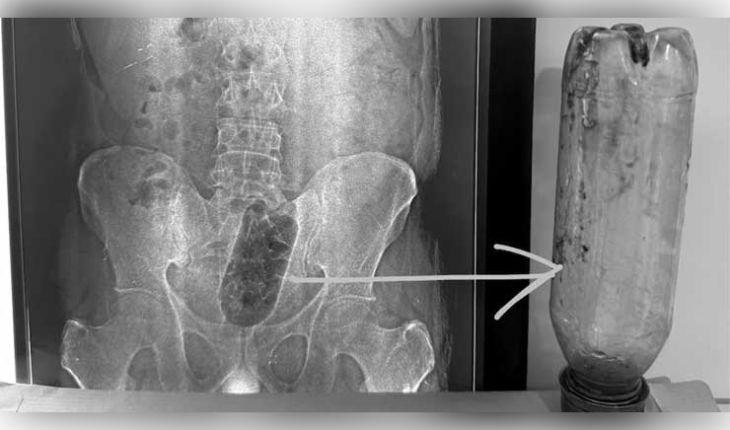

ଯନ୍ତ୍ରଣାରେ ଛଟପଟ ହେଉଥିବା ଯୁବକଙ୍କୁ ଆଗ୍ରାର ସାକେତ କଲୋନୀ ସ୍ଥିତ ନବଦୀପ ହସ୍ପିଟାଲରେ ଭର୍ତ୍ତି କରାଯାଇଥିଲା। ପ୍ରାଥମିକ ଯାଞ୍ଚ ଓ ଏକ୍ସ-ରେ (X-Ray) ରିପୋର୍ଟରୁ ଜଣାପଡିଥିଲା ଯେ ଯୁବକଙ୍କ ମଳାଶୟ ଭିତରେ ଏକ ବଡ଼ ପ୍ଲାଷ୍ଟିକ ବୋତଲ ଫସି ରହିଛି। ହସ୍ପିଟାଲର ବରିଷ୍ଠ ସର୍ଜନ ଡାକ୍ତର ସୁନୀଲ ଶର୍ମାଙ୍କ କହିବା ଅନୁଯାୟୀ, ଏହା ଏକ ଅତ୍ୟନ୍ତ ସମ୍ବେଦନଶୀଳ ମାମଲା ଥିଲା। ବୋତଲ ବାହାର କରିବା ସମୟରେ ଅନ୍ତନଳୀ ବା ମଳାଶୟ ଫାଟିଯିବାର ଆଶଙ୍କା ଥିଲା। ତେବେ ଡାକ୍ତରୀ ଦଳ ଅତ୍ୟନ୍ତ ସତର୍କତାର ସହ ପ୍ରାୟ ୧ ଘଣ୍ଟା ୧୦ ମିନିଟ୍ର ଜଟିଳ ଅସ୍ତ୍ରୋପଚାର କରିବା ପରେ ବୋତଲଟିକୁ ବାହାର କରିଥିଲେ।